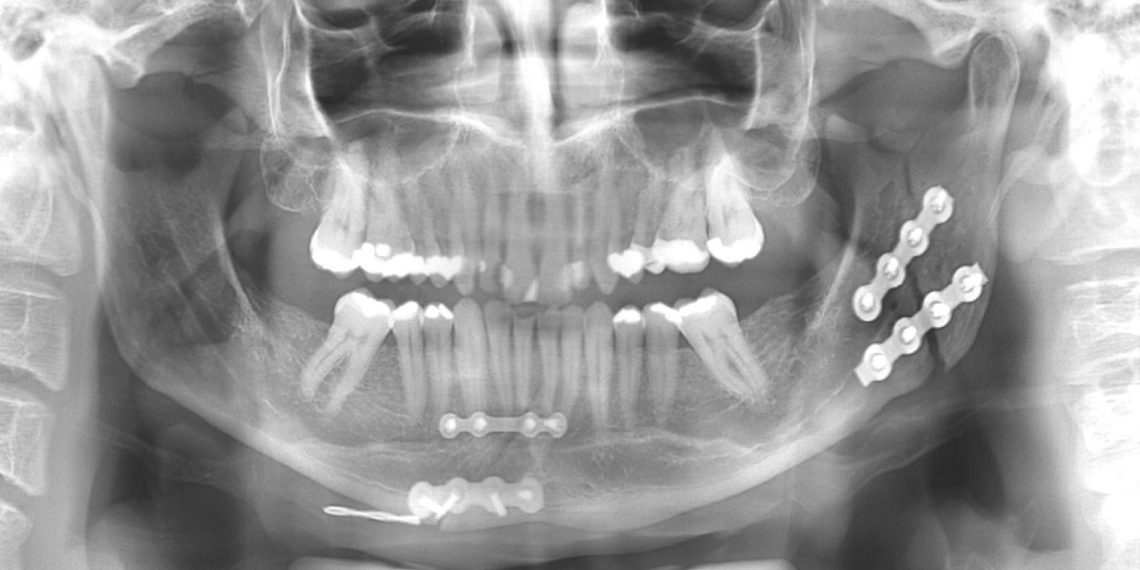

Nesses casos, o cirurgião buco-maxilo-facial é o profissional mais adequado para o tratamento das fraturas, ferimentos orais e faciais e tudo que está envolvido em todos os aspectos do tratamento.

Fraturas nos ossos da face também podem ocasionar desoclusão, que é a mordida errada dos dentes. Se não foram tratadas, podem ocasionar uma série de outros problemas funcionais.